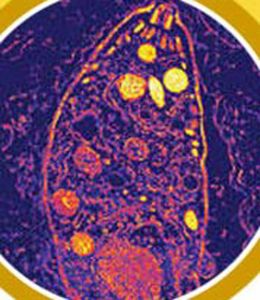

弓漿蟲(Toxoplasmosis)是一種單細胞原蟲,蟲體形狀像香蕉,寄生在許多溫血動物體內,其是鼠類和鳥類。宿主

弓漿蟲以貓為最終寄生體的寄生蟲。

弓蟲只能於貓體內進行有性生殖,於貓食入含有弓蟲囊體(cyst)的組織(生肉)後,弓蟲囊體便開始崩解並釋出分裂緩慢的裂殖子(bradyzoites),而這些裂殖子會於腸道壁內進行增殖,最終便會將所產生的卵囊(oocyst)釋放於糞便中而排出體外。

具感染能力的芽孢子化卵囊一旦被中間宿主(如:人、老鼠、犬、羊、豬等)食入之後,便會將其內的芽孢子(sporozoites)釋放出來,芽孢子會穿入腸壁並以分裂快速的裂殖子形式(tachyzoites)來進行無性增殖,使得芽孢子廣泛地散播於全身並在組織內形成囊體(cyst),而一旦貓生食了這些具有弓蟲囊體的組織(肉類食物),便完成了弓蟲的整個生活史。